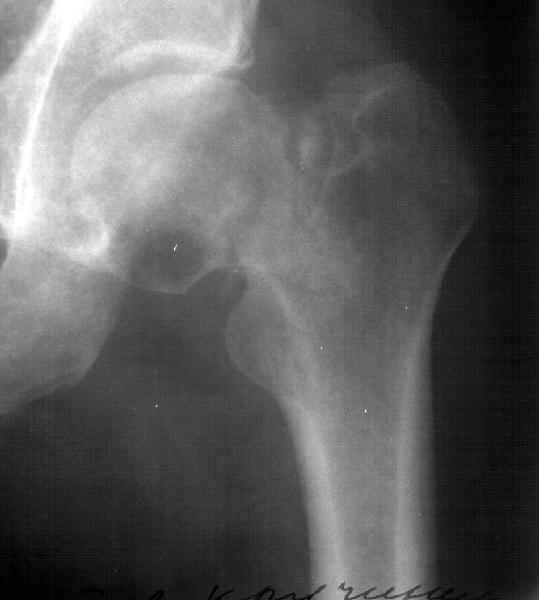

A miner 38 y.o. referred to us with 5 months old femoral neck lesion - after direct impact by a heavy construction he probably had non-displaced neck fracture. 3 months of spica cast, then non-weight-bearing. AP view and CT scan attached. Looks like AVN is present. ROM is painless and full, loading is also painless.